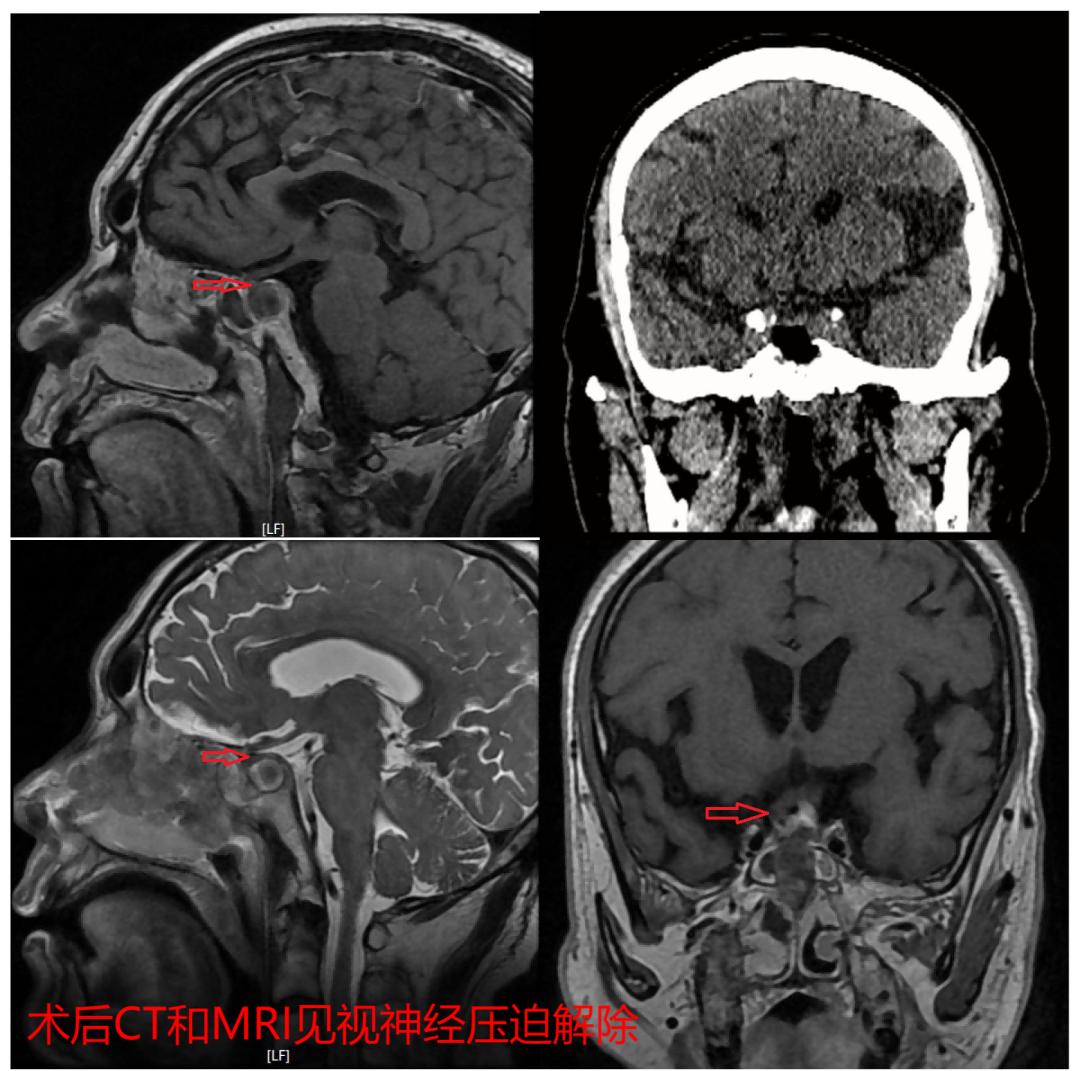

手术后48小时内复查的CT和MRI显示脑垂体瘤彻底切除,术区没有渗血,也没有肿瘤残留。术前出现的激素水平紊乱和电解质紊乱经过精心的调节后也恢复了正常。目前魏大爷已经顺利出院,在康复观察中。

经历了2个小时精密的神经内镜下手术治疗,魏大爷从麻醉状态下清醒了过来,很快恢复了正常的意识。“大爷,还头疼吗?”“不疼啦!”“眼睛能看清东西了吗?”“左眼清楚多了。”“右眼呢?”“右眼还是看不清,不过好像能看到亮了!”

同魏大爷的子女一样,神经外科的诊疗团队也非常的高兴和欣慰,一天来争分夺秒的努力没有白费,老人右眼的视力终于保住了,而且左眼的视力也有了明显的改善,失明的右眼再获光明!